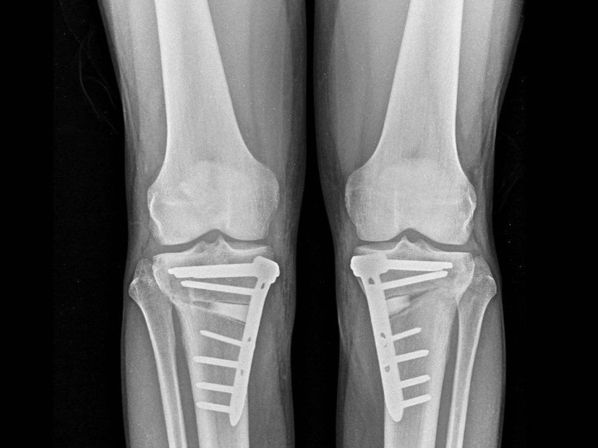

El doctor Juan Arnal, destacado especialista en Cirugía Ortopédica y Traumatología en el Hospital Universitario Gregorio Marañón de Madrid, ha resaltado la eficacia de la osteotomía para “retrasar durante décadas o, incluso, evitar la necesidad de una prótesis” de rodilla en pacientes con predisposiciones genéticas a la degeneración articular.

Esta intervención corrige anomalías en las piernas como el ‘genu varo’, que causa una curvatura externa de las rodillas, y el ‘genu valgo’, que provoca una forma en ‘X’ de las piernas, conservando la articulación natural y combatiendo la progresión de la artrosis sin recurrir a implantes protésicos.

AVANCES TECNOLÓGICOS

La técnica de la osteotomía se lleva a cabo mediante un corte preciso en el hueso (tibia o fémur) para ajustar la carga en la pierna, redistribuyendo el peso sobre la articulación y mitigando el dolor. El doctor Arnal ha destacado la transformación de esta técnica debido a avances como la planificación digital tridimensional y nuevos sistemas de fijación e implantes. “Hoy podemos planificar en el ordenador la corrección exacta y, si lo deseamos, imprimir en 3D guías quirúrgicas personalizadas. Además, los nuevos sistemas de fijación permiten que el paciente empiece a apoyar la pierna a las 24 horas”, explicó.